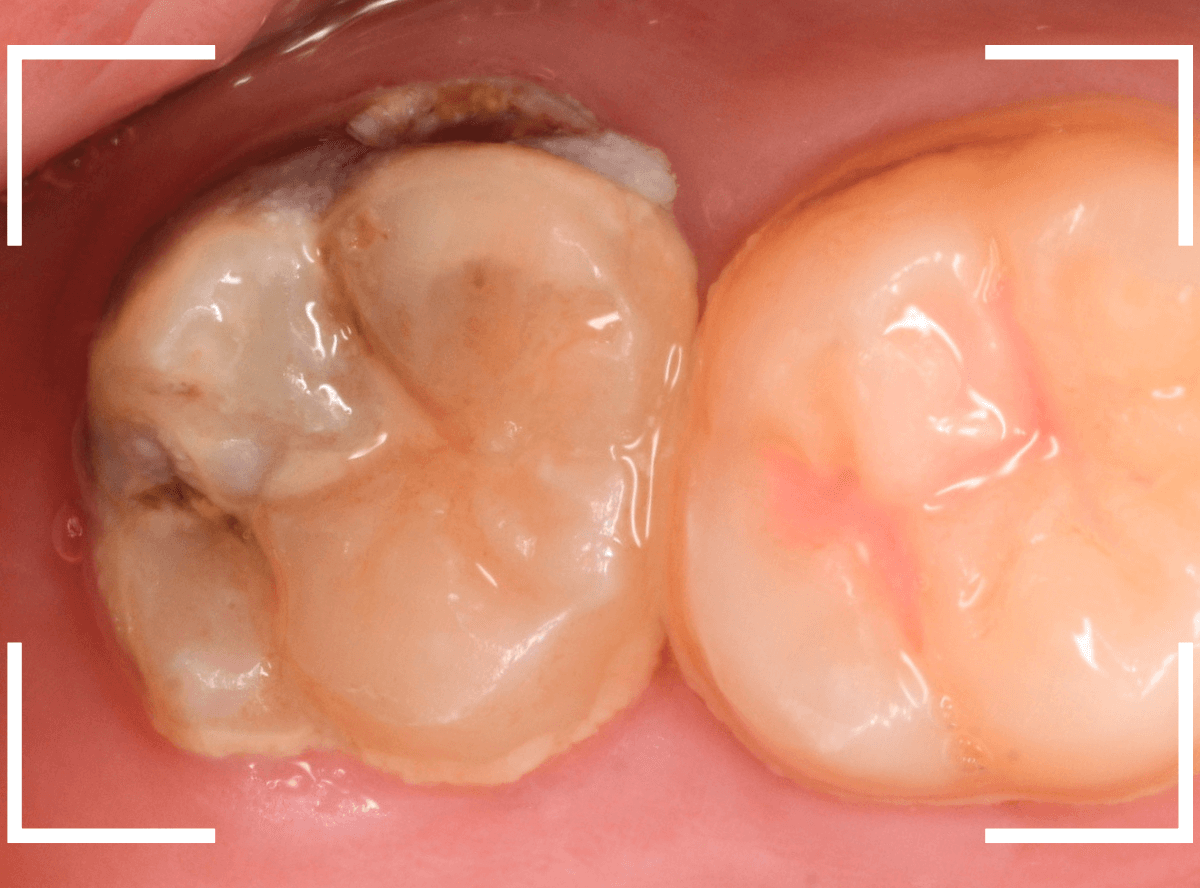

Case.9 隣の歯まで虫歯が進行していたケース

上の奥歯が痛むという訴えで来院された患者さんです。

一番奥の歯(左)が虫歯になっているのが一目でわかります。

虫歯も深そうです。

レントゲン写真で確認します。

赤い線が虫歯、青い線が歯の神経です。

歯の神経までは少し距離がありそうですが、深い虫歯であるのはわかります。

となりのつめもの(レジン)の下も虫歯になっているのがわかります。

治療を開始します。

赤く染まっている部分が虫歯です。

思った通り、かなり深く進行していますね。

奥歯の虫歯が全部除去できましたので、手前の歯の虫歯も治療します。

全ての虫歯を除去しました。

レントゲンから予測した通り、かなり広範な虫歯でした。

お薬をつめて、しばらく症状がないか経過観察後、つめものを作る治療に移ります。